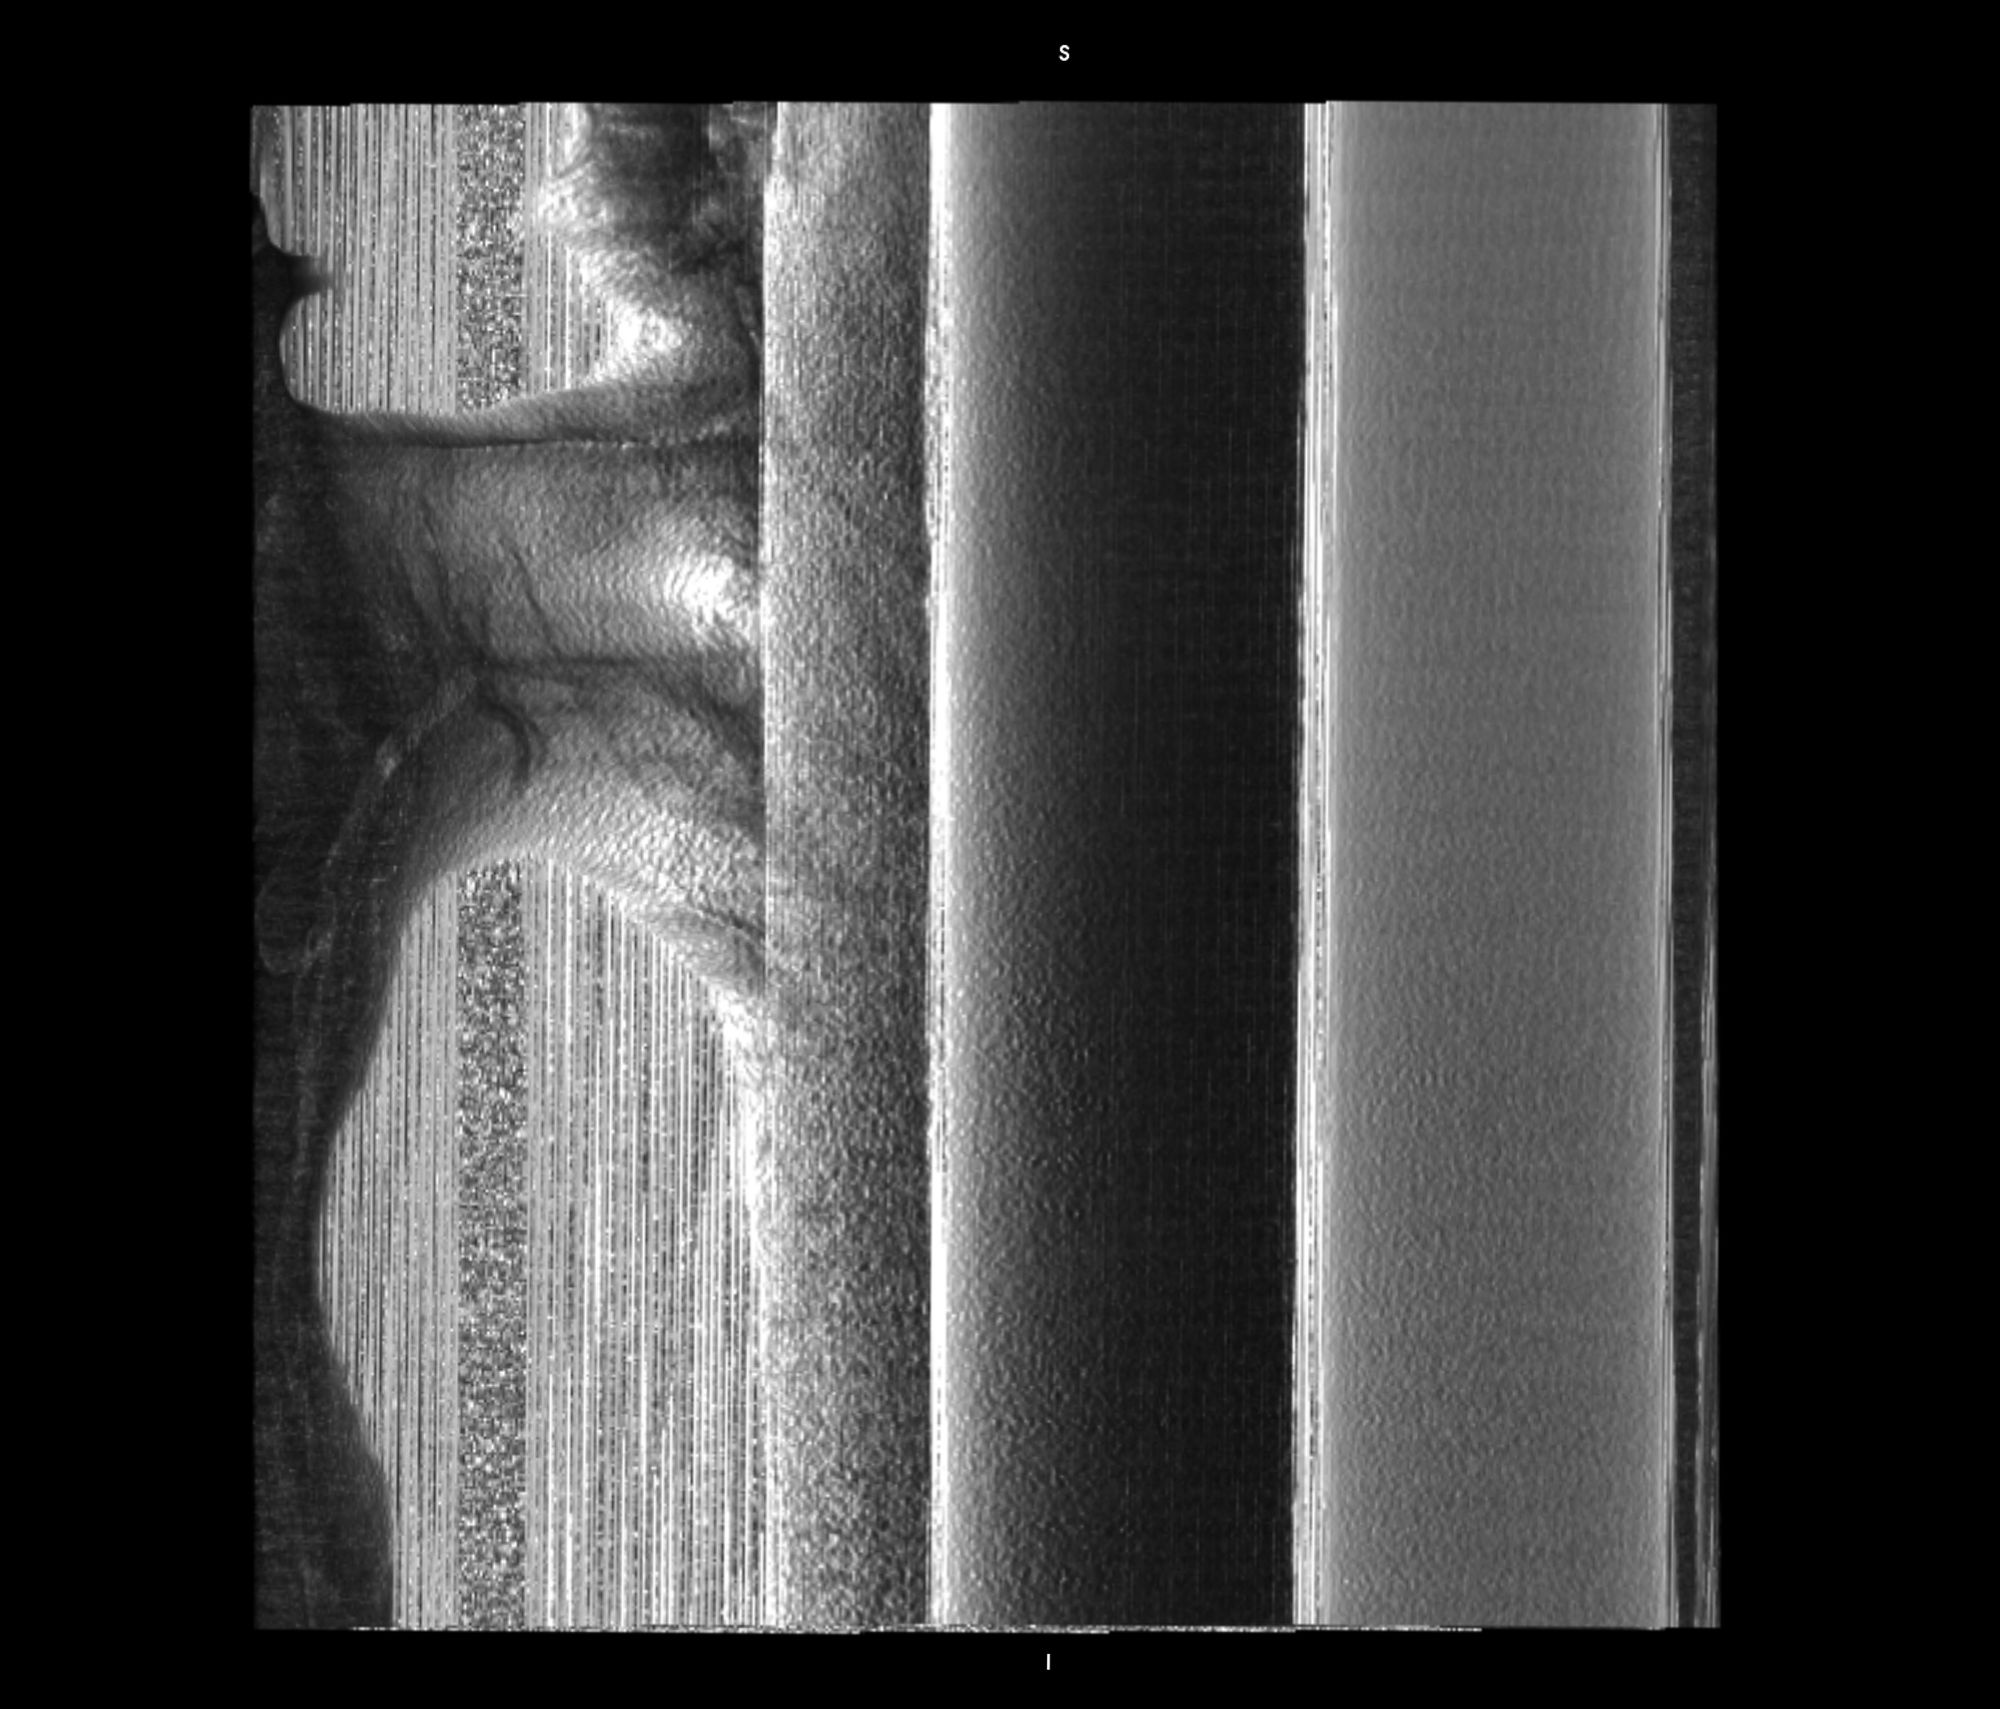

Chasing Intensities considers the body through its relationship to contemporary medical imaging technologies.

The history of medicine can be understood as an on-going endeavour to comprehensively visibilise the body, to pull it from obscurity, to open it out to vision. ‘The x-ray image, with its simultaneous view of the inside and outside, turned the vantage point of the spectator-subject inside out.’ * With the invention of the x-ray, the surface of the body, and its distinction from the world, was dissolved and lost in the image.

In this project, I look at the visual limit between the inside and the outside, the inner and the outer. I combine different visual approaches to materialise the body, using medical imagery, photography from manuals and radiology software. Decontextualised from their origin, these images speak of medicine’s relationship to both sex and violence, and remind us that, in medicine, to go into the body is always to go into the image first.